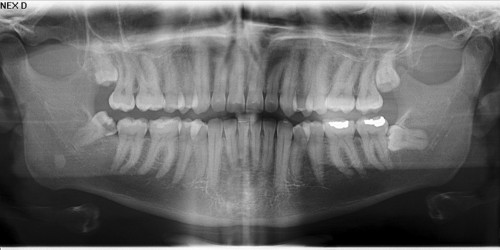

Hi, i am 19 y/o, i was diagnosed with tmj three years ago, i went to my dentist at first, he told me my problems were due to my wisdom teeth that were putting pressure, and to have physiotherapy, so i did. The physiotherapist said my problems were due to poor bine development and weak muscles, i had physio for 4 months, but it only worsened. Initially there was only pain, ringing in the ears, swelling, now my jaw cant open wide enough, then i went to a jaw specialist, he told me my problems were due to de-bite and to get braces to fix it, so i did get braces, but now my braces have come off and my problem still remains. One more thing, i am able to open my mouth fully when i apply pressure on the right sided joint, without applying pressure it hurts when i open, what could be the cause of my problem? I have tried everything in my power, went to every doctor that i could and my problem still remains, please help.